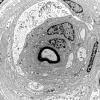

1K1A Massive Onion Bulbs (Case 1) EM 036 - Copy

1K1B Massive Onion Bulbs (Case 1) EM 038 - Copy

1K1C Massive Onion Bulbs (Case 1) EM 039 - Copy

1K1D Massive Onion Bulbs (Case 1) EM 040 - Copy

1K1E Massive Onion Bulbs (Case 1) EM 046 - Copy

1K1F Massive Onion Bulbs (Case 1) EM 049 - Copy

1K1G Massive Onion Bulbs (Case 1) EM 051 - Copy